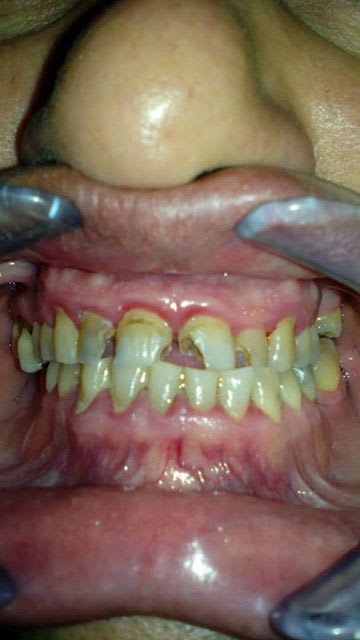

1) OHM

2) détartrage +/- assainissement paro

2) soins conservateurs : compo et endo

3) prothèse.